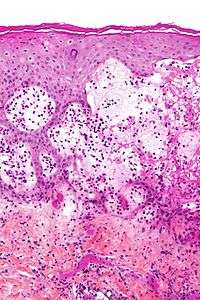

| Micrograph of gestational pemphigiod showing the characteristic subepidermal blisters and abundant eosinophils. HPS stain. | |